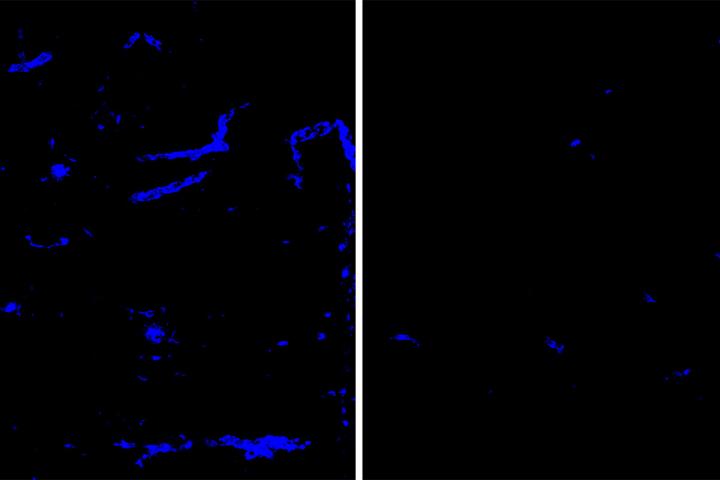

image: Amyloid deposits (blue) in mouse brain tissue and blood vessels are reduced after treatment with an antibody that targets the protein APOE (right), a minor component of amyloid deposits, compared to a placebo antibody (left). Amyloid deposits in the brain increase the risk of dementia and strokes. Researchers at Washington University School of Medicine in St. Louis have identified an antibody that clears amyloid deposits from the brain without raising the risk of brain bleeds.

Experiments showed that eight weeks of treating mice with HAE-4 reduced amyloid plaques in brain tissue and brain blood vessels. Treatment also significantly improved the ability of brain blood vessels to dilate and constrict on demand, an important sign of vascular health.